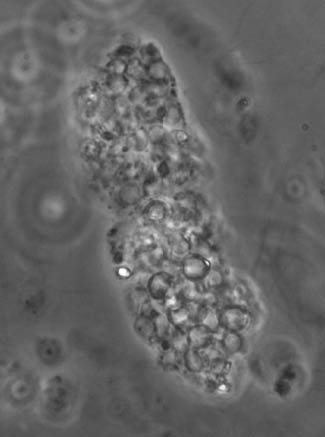

Cellular casts

These casts include all cylinders containing any type of cells which may be present in renal tubules such as leukocytes, erythrocytes and RTEC. Therefore, the classification of cellular casts encompasses leukocytic, erythrocytic, and RTEC casts.

Erythrocytic casts may contain different amounts of red blood cells (Figure 3). In some cases the number of erythrocytes is high and the presence of the matrix can be no longer distinguished.

An erythrocyte cast with packed erythrocytes (phase contrast microscope, original magnification 400×).

By courtesy of Dr. G.B. Fogazzi.

The presence of erythrocyte casts is considered a marker of glomerular hematuria, especially when they are associated with free dysmorphic erythrocytes in the urine. Erythrocyte casts are found in most glomerular diseases, especially in those with glomerular cell proliferation (the so-called proliferative glomerulonephritides) [15], although their frequency is highly variable among studies [7]. However, in contrast with the current view, erythrocyte casts can also be found in patients with acute interstitial nephritis (AIN), as it has been shown in a recent retrospective study on 21 patients with AIN due to different causes, six of whom had erythrocytic cylindruria (28.5%). It is hypothesised that in such cases the formation of erythrocyte casts might be the consequence of interstitial vessels injury secondary to interstitial cell inflammation, with extravasation of erythrocytes into the interstitial space and subsequent passage within the tubular lumens through tubular basement membranes breaks, which in AIN are very common [16].